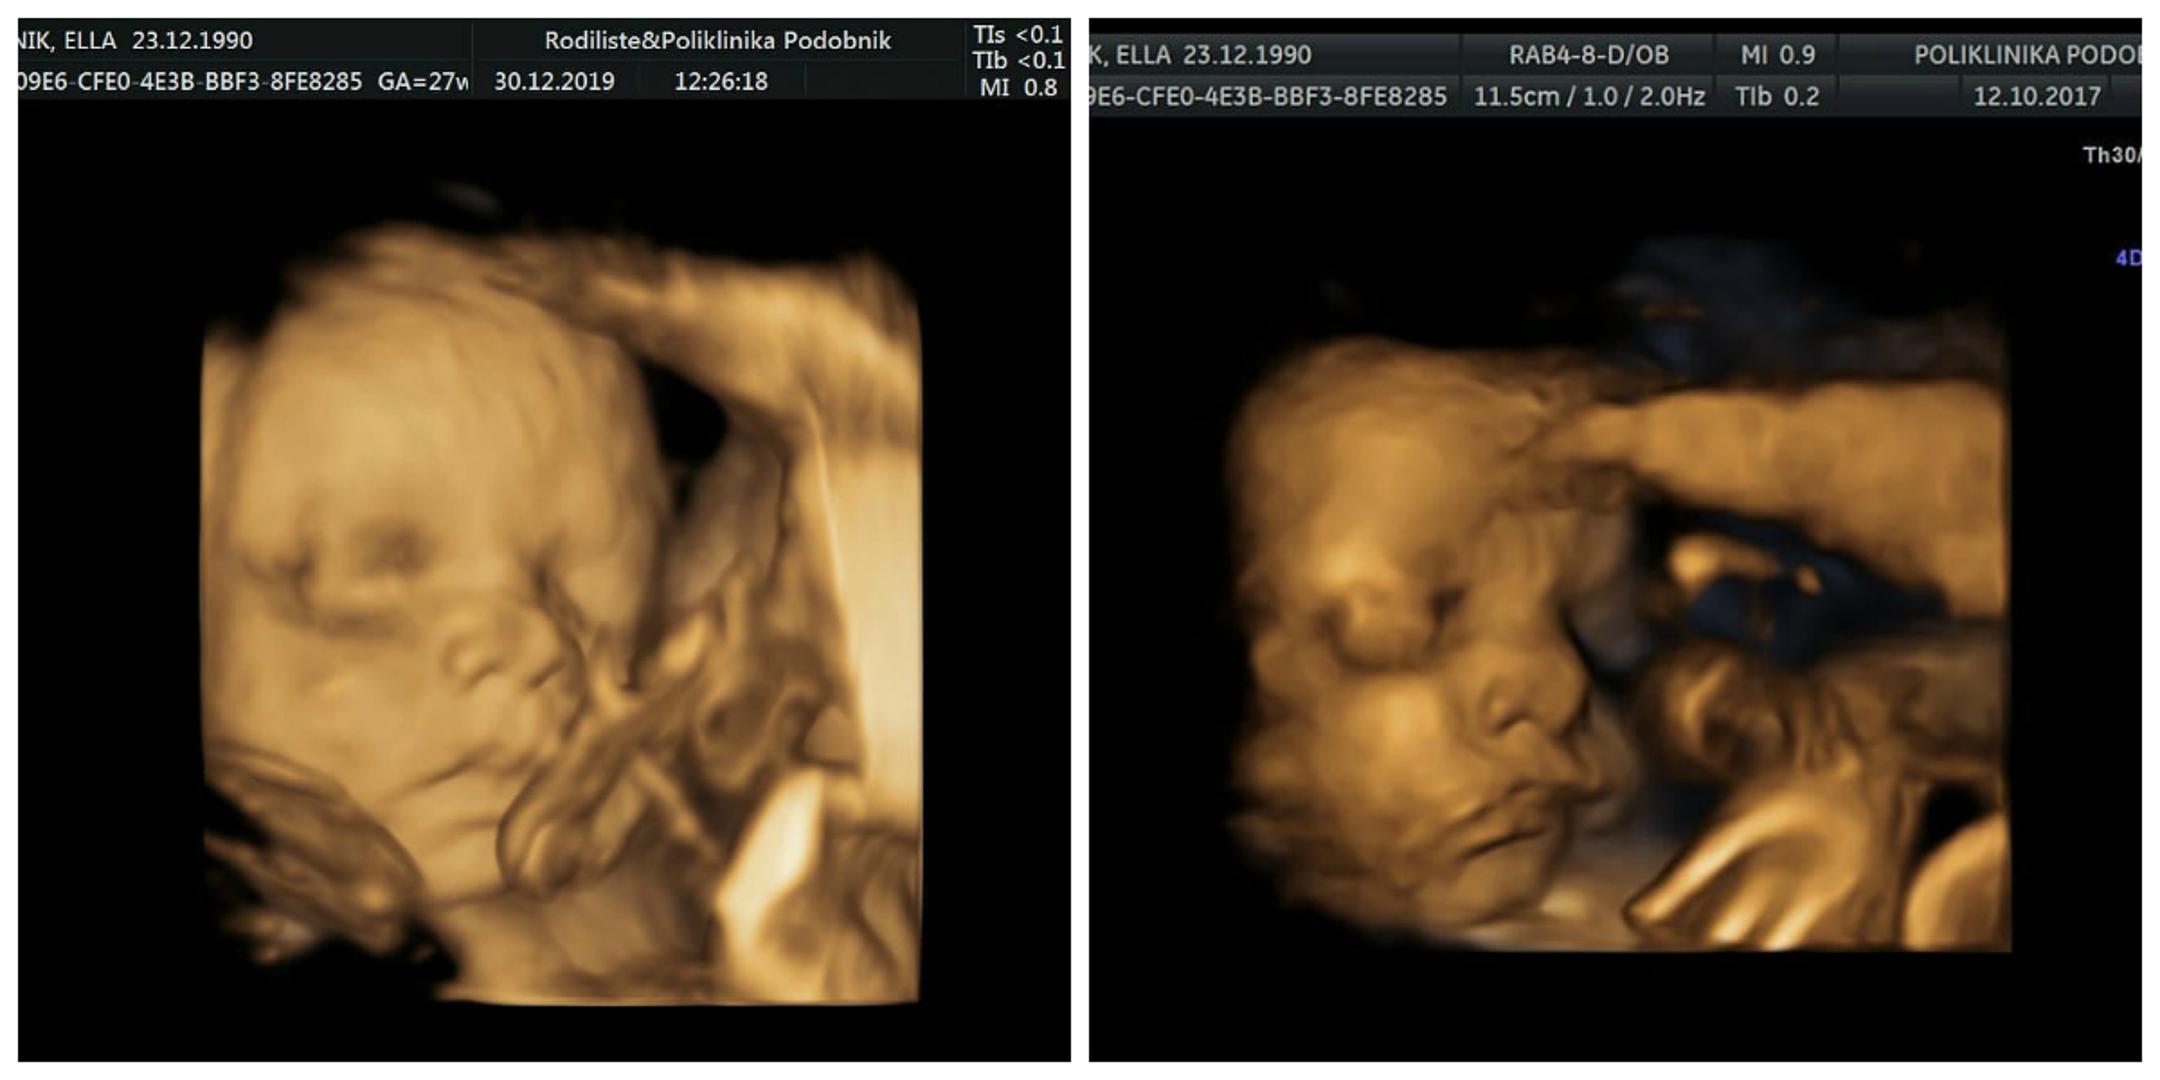

Podsjetimo, Ella je kćerkicu Balie rodila je prije dvije godine, a beba je zbog stanja u kojemu se Ella nalazila uranila četiri tjedna. Priznala je da je u 36. tjednu trudnoće dobila kolestazu i počela intenzivno povraćati. Kada je pomoć potražila kod svoje ginekologice, ona joj je savjetovala da se hitno spakira i dođe u bolnicu, a samo nekoliko dana kasnije počeo je inducirani porod.

– Nikako se nisam mogla otvoriti od pet do pola jedan. Onda su mi rekli da idem na hitan carski, prestravila sam se kad sam shvatila da će mi tu netko kopati po utrobi i da ću ja cijelo vrijeme biti budna. Kad su je izvadili, anesteziolog mi je dao nešto što je bilo kao da sam popušila pet jointa odjednom – ispričala je Ella.

Iako je rođena nekoliko tjedana ranije, Balie je bila dosta razvijena beba i sve je prošlo u najboljem redu.